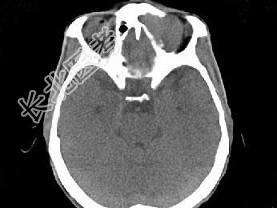

- 单项选择题男,53岁, 左眼痛、突出3年,结合图像, 最可能的诊断是 ( )

A、淋巴瘤

B、骨膜下脓肿

C、黏液囊肿

D、眼型Graves病

E、良性混合瘤